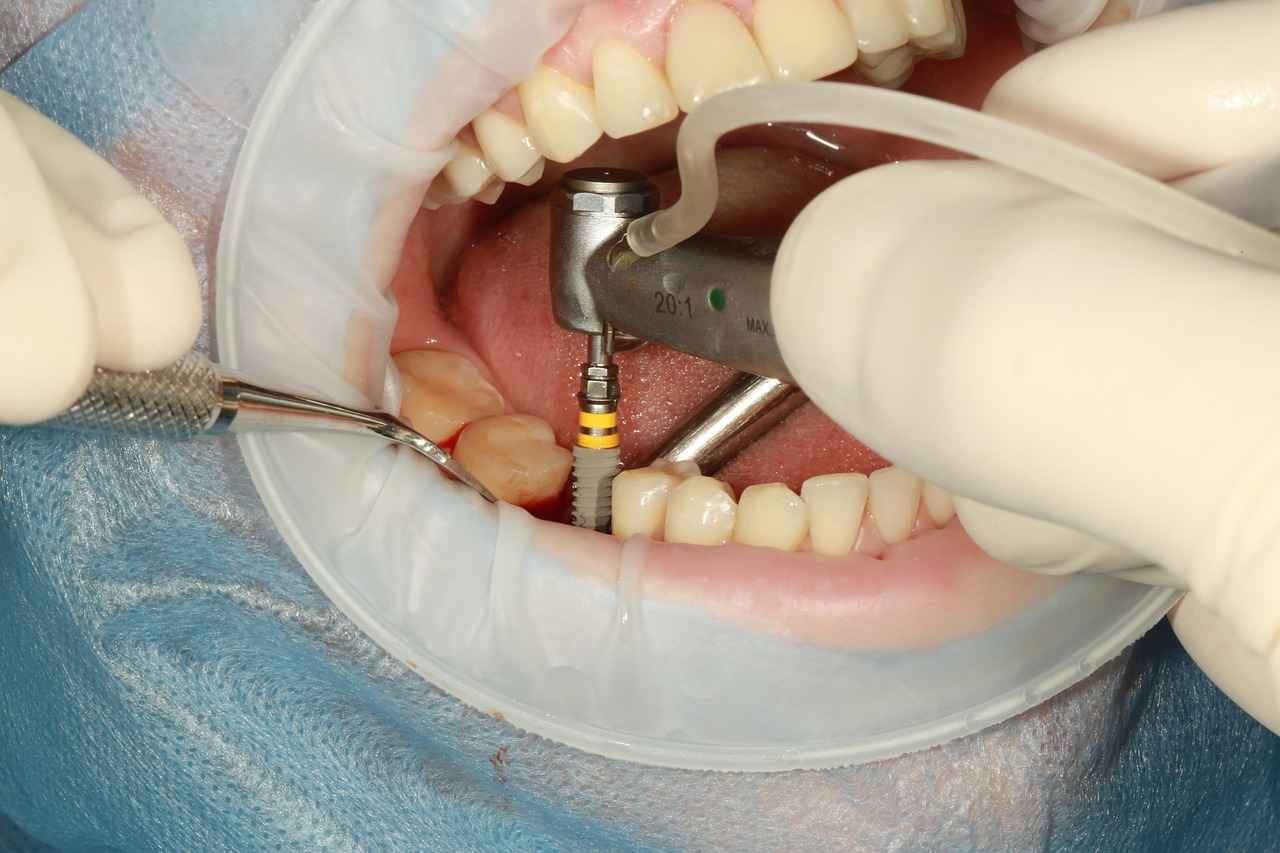

İmplantın yerleştirilme yöntemi, fiyatı etkileyen bir diğer önemli faktördür. Cerrahi teknikler ve sürecin karmaşıklığı maliyetleri etkileyebilir. Açık cerrahi yöntemler, genellikle daha fazla maliyet gerektirirken, kapatma cerrahisi daha az invaziv bir seçenek sunarak daha uygun fiyatlı olabilir. Ancak, her durum için uygun olmayabilir ve bu nedenle hastaların doktorlarıyla detaylı bir şekilde görüşmeleri önerilir.

İmplantın yerleştirilme yöntemi, dental implant tedavisinin en önemli aşamalarından biridir ve bu aşama, tedavi maliyetlerini doğrudan etkileyen bir faktördür. Uygulama yöntemi, cerrahın tercih ettiği teknikler, kullanılan ekipman ve sürecin karmaşıklığı gibi unsurlara bağlı olarak değişir. Bu makalede, implant yerleştirme yöntemlerini ve bunların fiyatlar üzerindeki etkilerini detaylı bir şekilde inceleyeceğiz.

İmplant yerleştirme yöntemleri, genellikle iki ana kategoriye ayrılır: açık cerrahi yöntemler ve kapatma cerrahisi. Her iki yöntem de farklı avantajlar ve dezavantajlar sunar.

Açık cerrahi yöntemler, genellikle daha invaziv bir yaklaşım olarak kabul edilir. Bu yöntemler, hastanın çene yapısına ve implantın yerleştirileceği bölgeye bağlı olarak değişiklik gösterebilir. Açık cerrahi, genellikle daha fazla uzmanlık ve ekipman gerektirir, bu nedenle maliyetler de daha yüksek olabilir.

Açık cerrahi yöntemler, implantın yerleştirilmesi için diş etinin açılması ve diş kökünün doğrudan görünür hale getirilmesi gereken tekniklerdir. Bu yöntem, özellikle kemik yapısının zayıf olduğu veya implantın yerleştirileceği alanda daha fazla müdahale gerektiren durumlarda tercih edilir. Açık cerrahi yöntemlerin uygulanabilmesi için genellikle daha fazla uzmanlık ve tecrübe gerekmektedir.